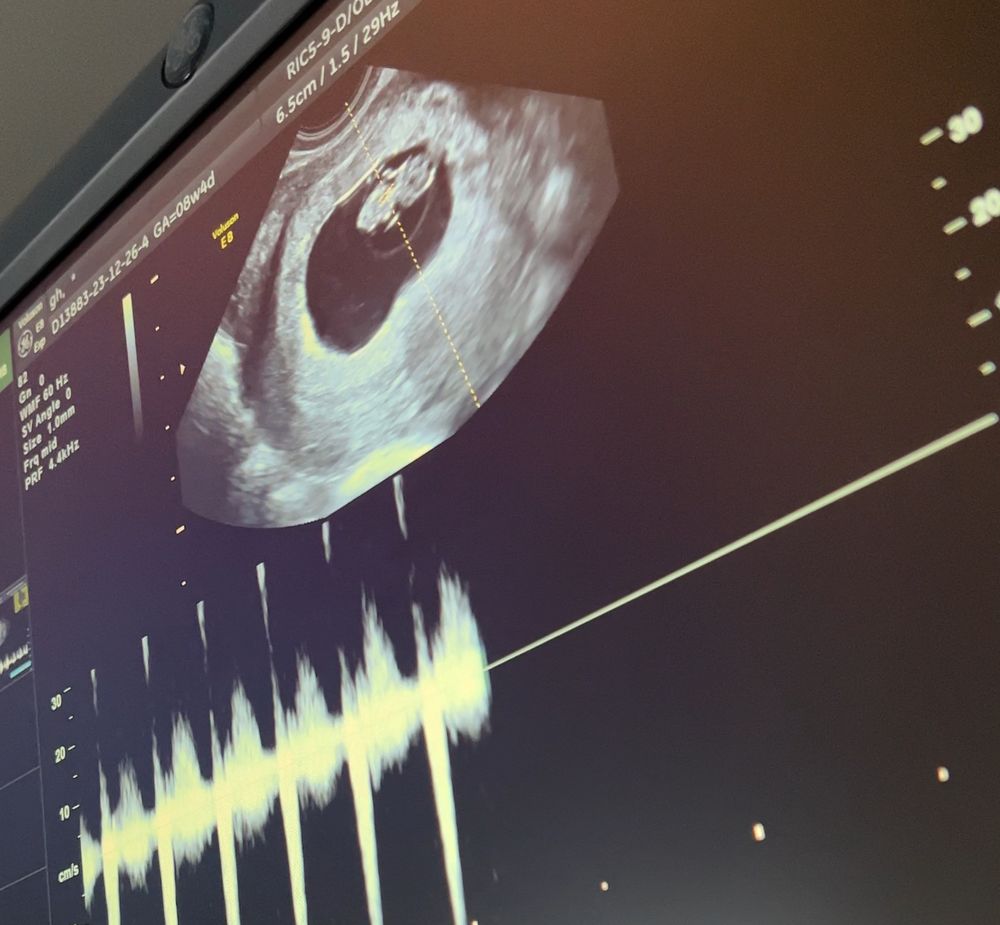

Я бы на вашем месте сдавала бы хгч через день, а на узи не торопилась. На узи вам если и что-то скажут, так это что пя в матке. Даже возможно жм не увидят еще. А про эмбрион и сердечко вообще молчу. И потом вы снова будете себя накручивать. Сдайте хотя бы 2-3 раза хгч, посмотрите прирост, а потом на 7-8 неделе можно смело на узи

Queen, я записана на 30.01 на узи) тогда если считать от месячных у меня будет ровно 7 недель)) поэтому не хочу из-за оставшейся недельки сдавать( больше не буду делать тесты и изводить себя

Гость, через пару дней повторите , убедитесь. Потом дождитесь срока 7-8 недели (посчитайте) и сходите на узи , уже и эмбрион будет видно, и сердечко🙏